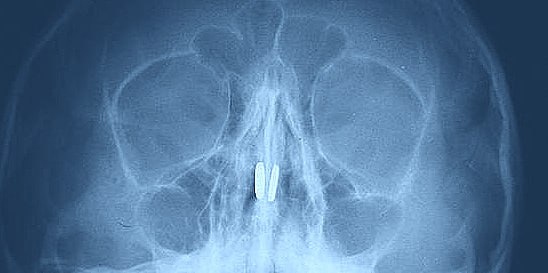

Нижегородские врачи извлекли магнитные шарики, застрявшие в носу у шестилетнего мальчика. Об этом сообщил Тelegram-канал "Бокал прессека".

Во время осмотра врач ЛОР-отделения Медскрин областного Центра по борьбе со СПИД Валерия Наумова обнаружила в носовых ходах ребенка по одному магниту. Игрушечные шарики притянулись друг к другу, зажав носовую перегородку между собой.

Инородные тела были аккуратно извлечены с помощью специального медицинского крючка. Повреждений перегородки удалось избежать, а незначительное воспаление слизистой, по словам врача, пройдет в ближайшее время.

Специалист подчеркнула, что при длительном нахождении магнитов в носу могут возникнуть серьезные осложнения — от кровотечений до перфорации перегородки.